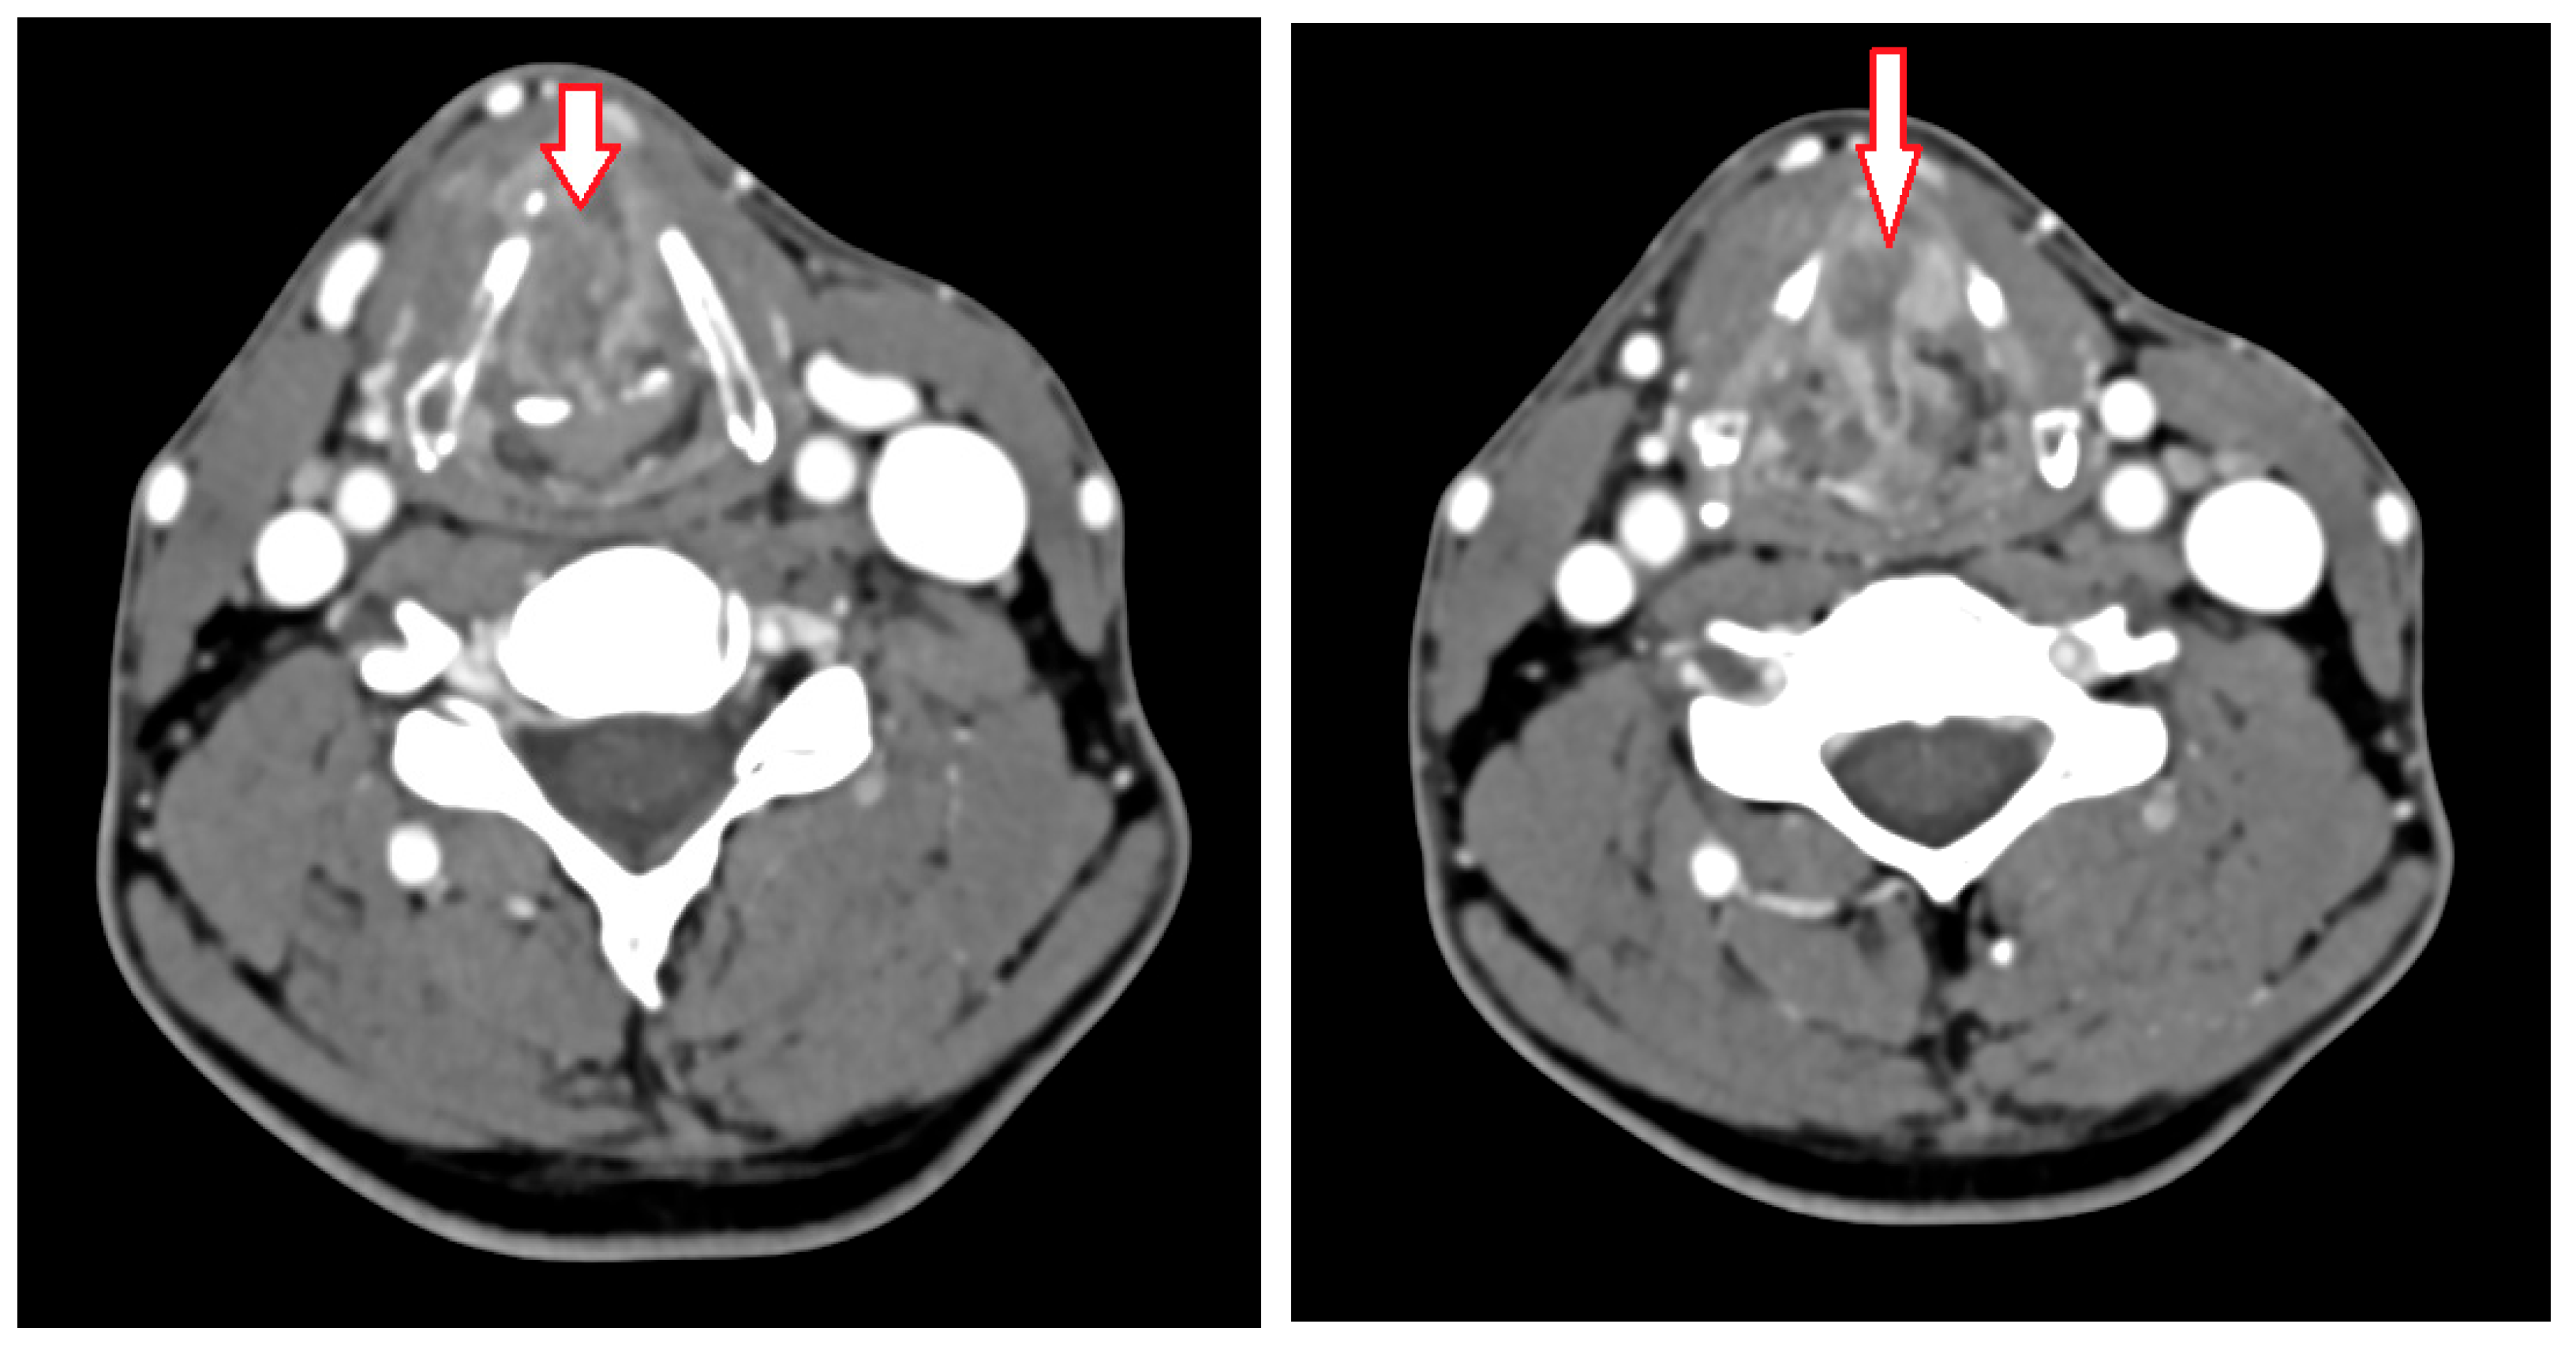

2. Case Presentation